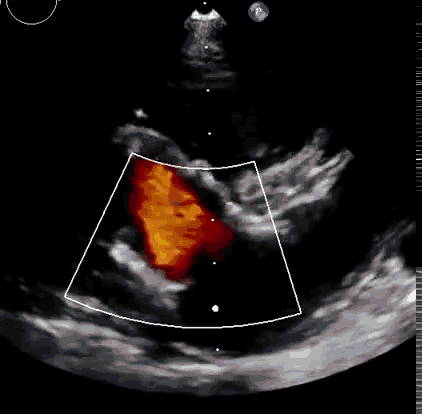

上海中山医院葛均波院士、钱菊英院长、周达新教授、潘文志教授、潘翠珍教授、李伟教授共同完成此次临床前研究。术后葛均波院士对Lux-Valve Plus的器械操作性能给予了高度评价,DSA和超声影像也显示出在本次研究中Lux-Valve Plus的安全性和有效性俱佳。

本次临床前研究经右侧颈静脉置入LuX-Valve Plus输送系统可调弯鞘管,在DSA及超声引导下将人工三尖瓣瓣膜植入到原有三尖瓣位置,利用独特的锚定技术将人工瓣膜支架可靠固定在预定的位置。

Lux-Valve是全球第一款具有我国完全自主知识产权的经导管介入三尖瓣置换系统,利用前瓣夹持及室间隔锚定的复合方式进行瓣膜装置的固定,不依赖瓣环径向支撑力,同时采用自适应复合裙边材料,有效的贴合密封柔软的三尖瓣瓣环,针对于三尖瓣返流的患者有优异的疗效。Lux-Valve Plus采用全新的经血管输送系统,经颈静脉入路创伤更小,可以进一步降低手术风险。相信在后期正式临床研究开展中,Lux-Valve Plus必定会为更多的三尖瓣反流患者带来福音。